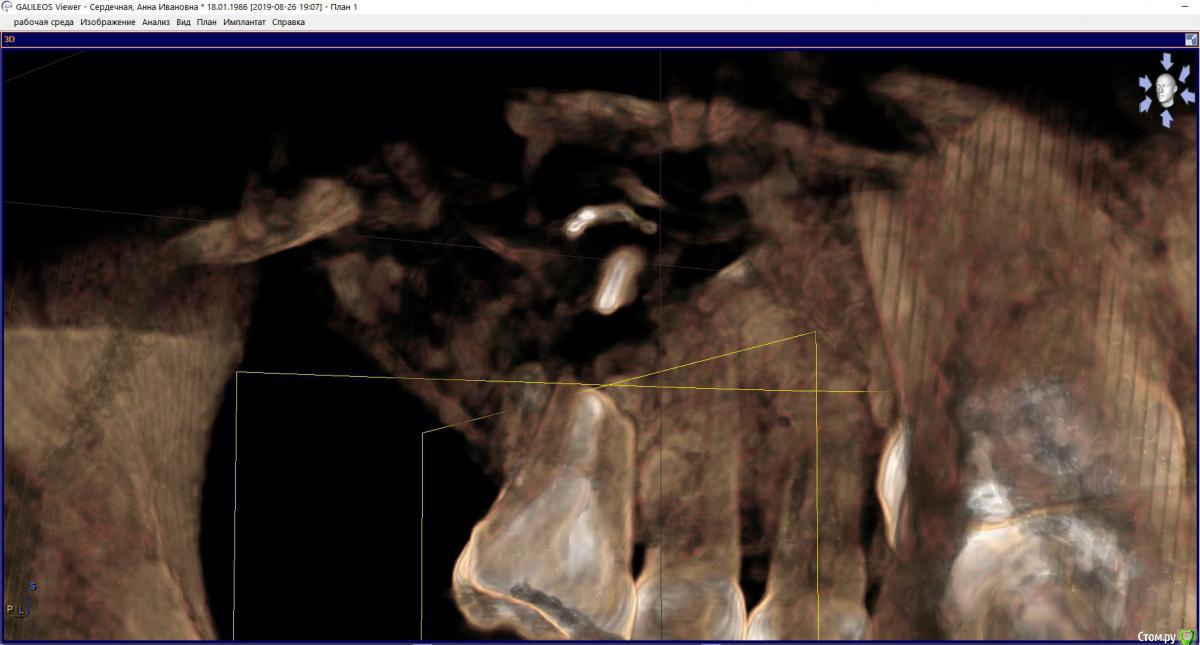

hichin Опубликовано 27 августа, 2019 Поделиться Опубликовано 27 августа, 2019 Здравствуйте, уважаемые стоматологи! Проблемный многострадальный зуб-моляр (26): Дважды попытки удаления кисты левой г/п, вторая попытка удачная, а также гайморотомия и септопластика.Неудачное эндодонтическое лечение, далее повторная попытка перелечивания (смена паст, симптоматика не уходила), которая закончилась сменой стоматолога и лечением с микроскопом. После пломбировки каналов снизилась симптоматика, но пазуха все равно реагировала небольшим утолщением слизистой + любая простуда давала сильную боль на пазуху + зуб. Врачи клиники советовали сделать резекцию. Лоры говорили, что проблема не с их стороны. В члх сделали резекцию с обратной пломбировкой.P.s. так долго эпопея с зубом длится, т.к. все специалисты в один голос говорили о том, что удаление зуба и последующая установка имплантата не факт, что избавит от проблем и будет вообще возможна.Симптоматика c резекцией не ушла.Срезы из свежего КТ прикрепляю. Если можно, прокомментируйте, пожалуйста, срезы. Ссылка на комментарий

колесников Опубликовано 27 августа, 2019 Поделиться Опубликовано 27 августа, 2019 Здравствуйте! По этим срезам изменения а пазухе не значительные,в пределах нормы,характерные для хронического процесса,наличие или отсутствие моляра на него никак не скажется,это самостоятельное заболевание. Над моляром достаточно по..работали,в перспективе он удаляется и замещается на имплант 1 Ссылка на комментарий

hichin Опубликовано 28 августа, 2019 Автор Поделиться Опубликовано 28 августа, 2019 Здравствуйте! По этим срезам изменения а пазухе не значительные,в пределах нормы,характерные для хронического процесса,наличие или отсутствие моляра на него никак не скажется,это самостоятельное заболевание. Над моляром достаточно по..работали,в перспективе он удаляется и замещается на имплант Благодарю вас за ответ.А как быть с оставшимся фрагментом небного корня (если я правильно понимаю, врач удалил не верхушку корня, а как бы середину корня). Реально ли его извлечь и как (через лунку удаленного зуба, через пазуху, тем же путем, что не дошел врач члх)? Основная симптоматика как раз с небной стороны у меня. Ссылка на комментарий

колесников Опубликовано 28 августа, 2019 Поделиться Опубликовано 28 августа, 2019 Или небным доступом или через лунку 1 Ссылка на комментарий